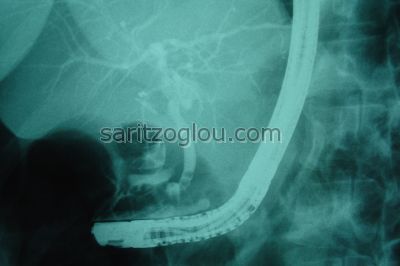

Μεγάλη διάταση του χοληδόχου πόρου λόγω, απόφραξής του, συνεπεία χοληδοχολιθίασης. Απεικονίζεται η παρουσία μεγάλου λίθου.

Χοληδοχολιθίαση. Έγινε λιθοτριψία και τοποθέτηση pig-tail stent Aαπεικόνιση υπολοιπόμενου λίθου εντός του πόρου.